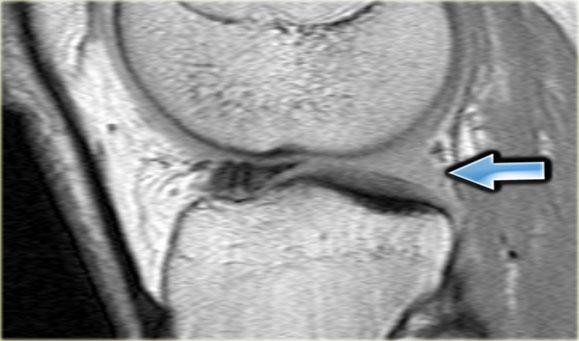

Bên trái là một trường hợp sụn chêm lật khác.

Lần này ở phía trong (medial).

Một phần sừng trước bị lật ra phía sau.

Chỉ một phần nhỏ của sừng trước được nhìn thấy ở phía trước.

Hầu hết các trường hợp sụn chêm lật xảy ra ở phía ngoài (lateral).

Dây chằng chéo trước (ACL) ngăn mảnh sụn chêm di chuyển hoàn toàn vào hố gian lồi cầu.

Trên hình ảnh mặt phẳng coronal, trước tiên sẽ thấy sừng trước to và phồng lên.

Ở phía sau sẽ thấy sừng sau rất nhỏ.